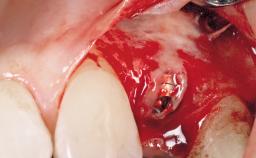

A 30-year-old female patient was referred to the office for the treatment of tooth 11. Her chief concern at the initial visit was to inquire, “Why is my tooth pink?” Upon clinical examination, it was determined that tooth 11 had a previous history of trauma and that the clinical crown had become noticeably pink in color as a result of internal resorption. This diagnosis was confirmed radiographically, indicating a large radiolucency involving the central and distal portions of the clinical crown. It was determined that restoration of this tooth was not possible, and that extraction was indicated. The presence of a mid-line diastema, which the patient wanted to reproduce, directed the treatment plan for tooth replacement utilizing a dental implant.

Placement Protocol Immediate implant placement

Socket Morphology Single-root socket

Socket Integrity Sufficient, with intact bone walls

Bone Volume Sufficient, with intact walls